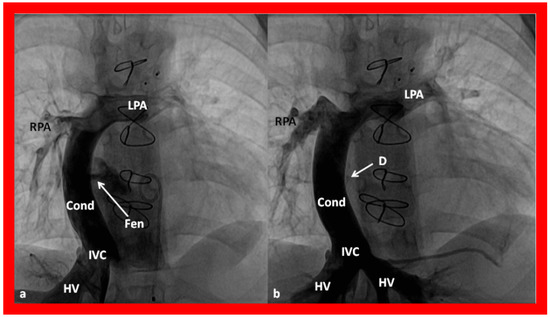

Angiographic counter part of the Fontan conduit with fenestration is shown, in Figure 54, to have better comprehension of the anatomy of the Fontan.

Figure 24. Selected cine frames in postero–anterior (a) and lateral (b) views, demonstrating a Blalock–Taussig (BT) shunt (arrow in a) to care for infants with decreased pulmonary blood flow (a) and pulmonary artery banding (PB) (arrow in (b)) in babies with increased pulmonary blood flow (b), respectively, during Stage I of Fontan procedure. C, catheter; LPA, left pulmonary artery; RPA, right pulmonary artery. Neonates with adequate pulmonary blood flow do not need any intervention and can go directly to Stage II at about the age of 3 months. Reproduced from Rao PS, Indian J Pediatr 2015;82:1147–1156 [36].